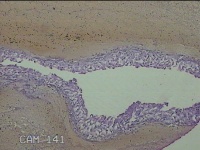

左侧卵巢黄体

性别

女

年龄

34岁

临床诊断

左侧卵巢黄体破裂

一般病史

下腹疼痛11小时。

标本名称

大体所见

灰白暗红色囊壁样组织3x2.3x0.3cm一堆,表面光滑,内壁高低不平,切面灰白暗红色,囊壁厚约0.1cm。

黄体囊肿?

有可能,所提供图片不具有诊断价值。